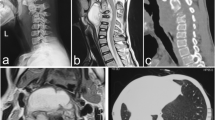

The baseline demographic details of the deformity and osteotomy of these patients are summarized in Table 1 (Fig. 1). Details of late-onset neurological deficits, including preoperative status and postoperative improvement, are summarized in Table 2 (Fig. 2).

Causes of late-onset neurological deficits according to the lesions. a, b Preoperative magnetic resonance image (MRI) and computed tomography (CT) scanning demonstrate severe angular kyphosis, “buckling collapse” from T9 to L3, intervertebral disc herniation and calcified ligamentum flavum at T8/9, and severe spinal cord compression. c, d Preoperative MRI and CT scanning demonstrate severe angular kyphosis from T8 to T10, calcified ligamentum flavum at T7/8 and T10/11, and severe spinal cord compression. e, f Preoperative MRI and CT scanning demonstrate severe angular kyphosis, “buckling collapse” from T10 to L2, intervertebral disc herniation and calcified ligamentum flavum at T10/11, and severe spinal cord compression. g, h Preoperative MRI and CT scanning demonstrate severe angular kyphosis, “buckling collapse” from T8 to L2, calcified ligamentum flavum at T10/11, and severe spinal cord compression. i, j Preoperative MRI and CT scanning demonstrate severe angular kyphosis, intervertebral disc herniation and calcified ligamentum flavum at T9/10, and severe spinal cord compression. *Calcified ligamentum flavum at the segments adjacent to the angular kyphosis; #disc herniation at the segments adjacent to the angular kyphosis

Stenosis adjacent to the angular kyphosis, which may be an important reason of late-onset neurological deficits and risk factor for neurological complications during PVCR, can be caused by intervertebral disc degeneration and/or calcification of ligamentum flavum at the adjacent segments. Mechanical stress may be the cause for intervertebral disc degeneration and calcification of ligamantum flavum at the adjacent segments [33]. Luk and Krishna [34] reported two cases with late-onset neurological deficits caused by spinal stenosis above healed tubercular kyphosis. Chen et al. [35] found ossification of the ligamentum flavum at segments adjacent to the kyphotic apex in six patients with thoracic tuberculosis. Ha et al. [7] reported ten cases with late-onset neurological deficits, including ossified ligament flavum (four), spinal stenosis (four), and intervertebral disc herniation (two). In the present study, five cases with late-onset neurological deficits were confirmed with stenosis at the segments adjacent to the apex of angular kyphosis (Table 2, Fig. 2).